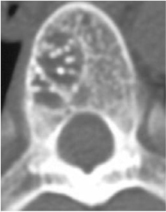

Смешанная гемангиома

Смешанные гемангиомы по структуре состоят как из тонкостенных сосудов, так и кавернозных полостей. Значение этих гемангиома зависит от объема поражения тела позвонка данной сосудистой опухолью.

Смешанные гемангиомы по структуре состоят как из тонкостенных сосудов, так и кавернозных полостей. Значение этих гемангиома зависит от объема поражения тела позвонка данной сосудистой опухолью.